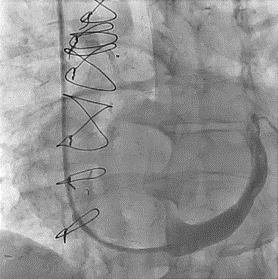

After the right transjugular puncture and introducer implantation, the coronary sinus (CS) was catheterized (Figure, A; Video 1). A CSR was advanced to the targeted implantation site in the mid-segment of the CS. The guiding catheter was then retracted, and the balloon was inflated to expand the CSR at the implantation site. After deflation, the balloon was retrieved. During the extraction of the deflated balloon, under fluoroscopy, we observed device migration into the right atrium while being attached at the tip of the catheter (Figure, B; Video 2). To snare the reducer, a 14-French sheath was advanced in the right femoral vein. We attempted to keep the wire inside the stent, but the prothesis migrated to the left pulmonary artery without the possibility of recovering it using the lasso technique (Figure, C; Video 3). We decided to implant a second CSR more distally in the CS (Figure, D; Video 4).